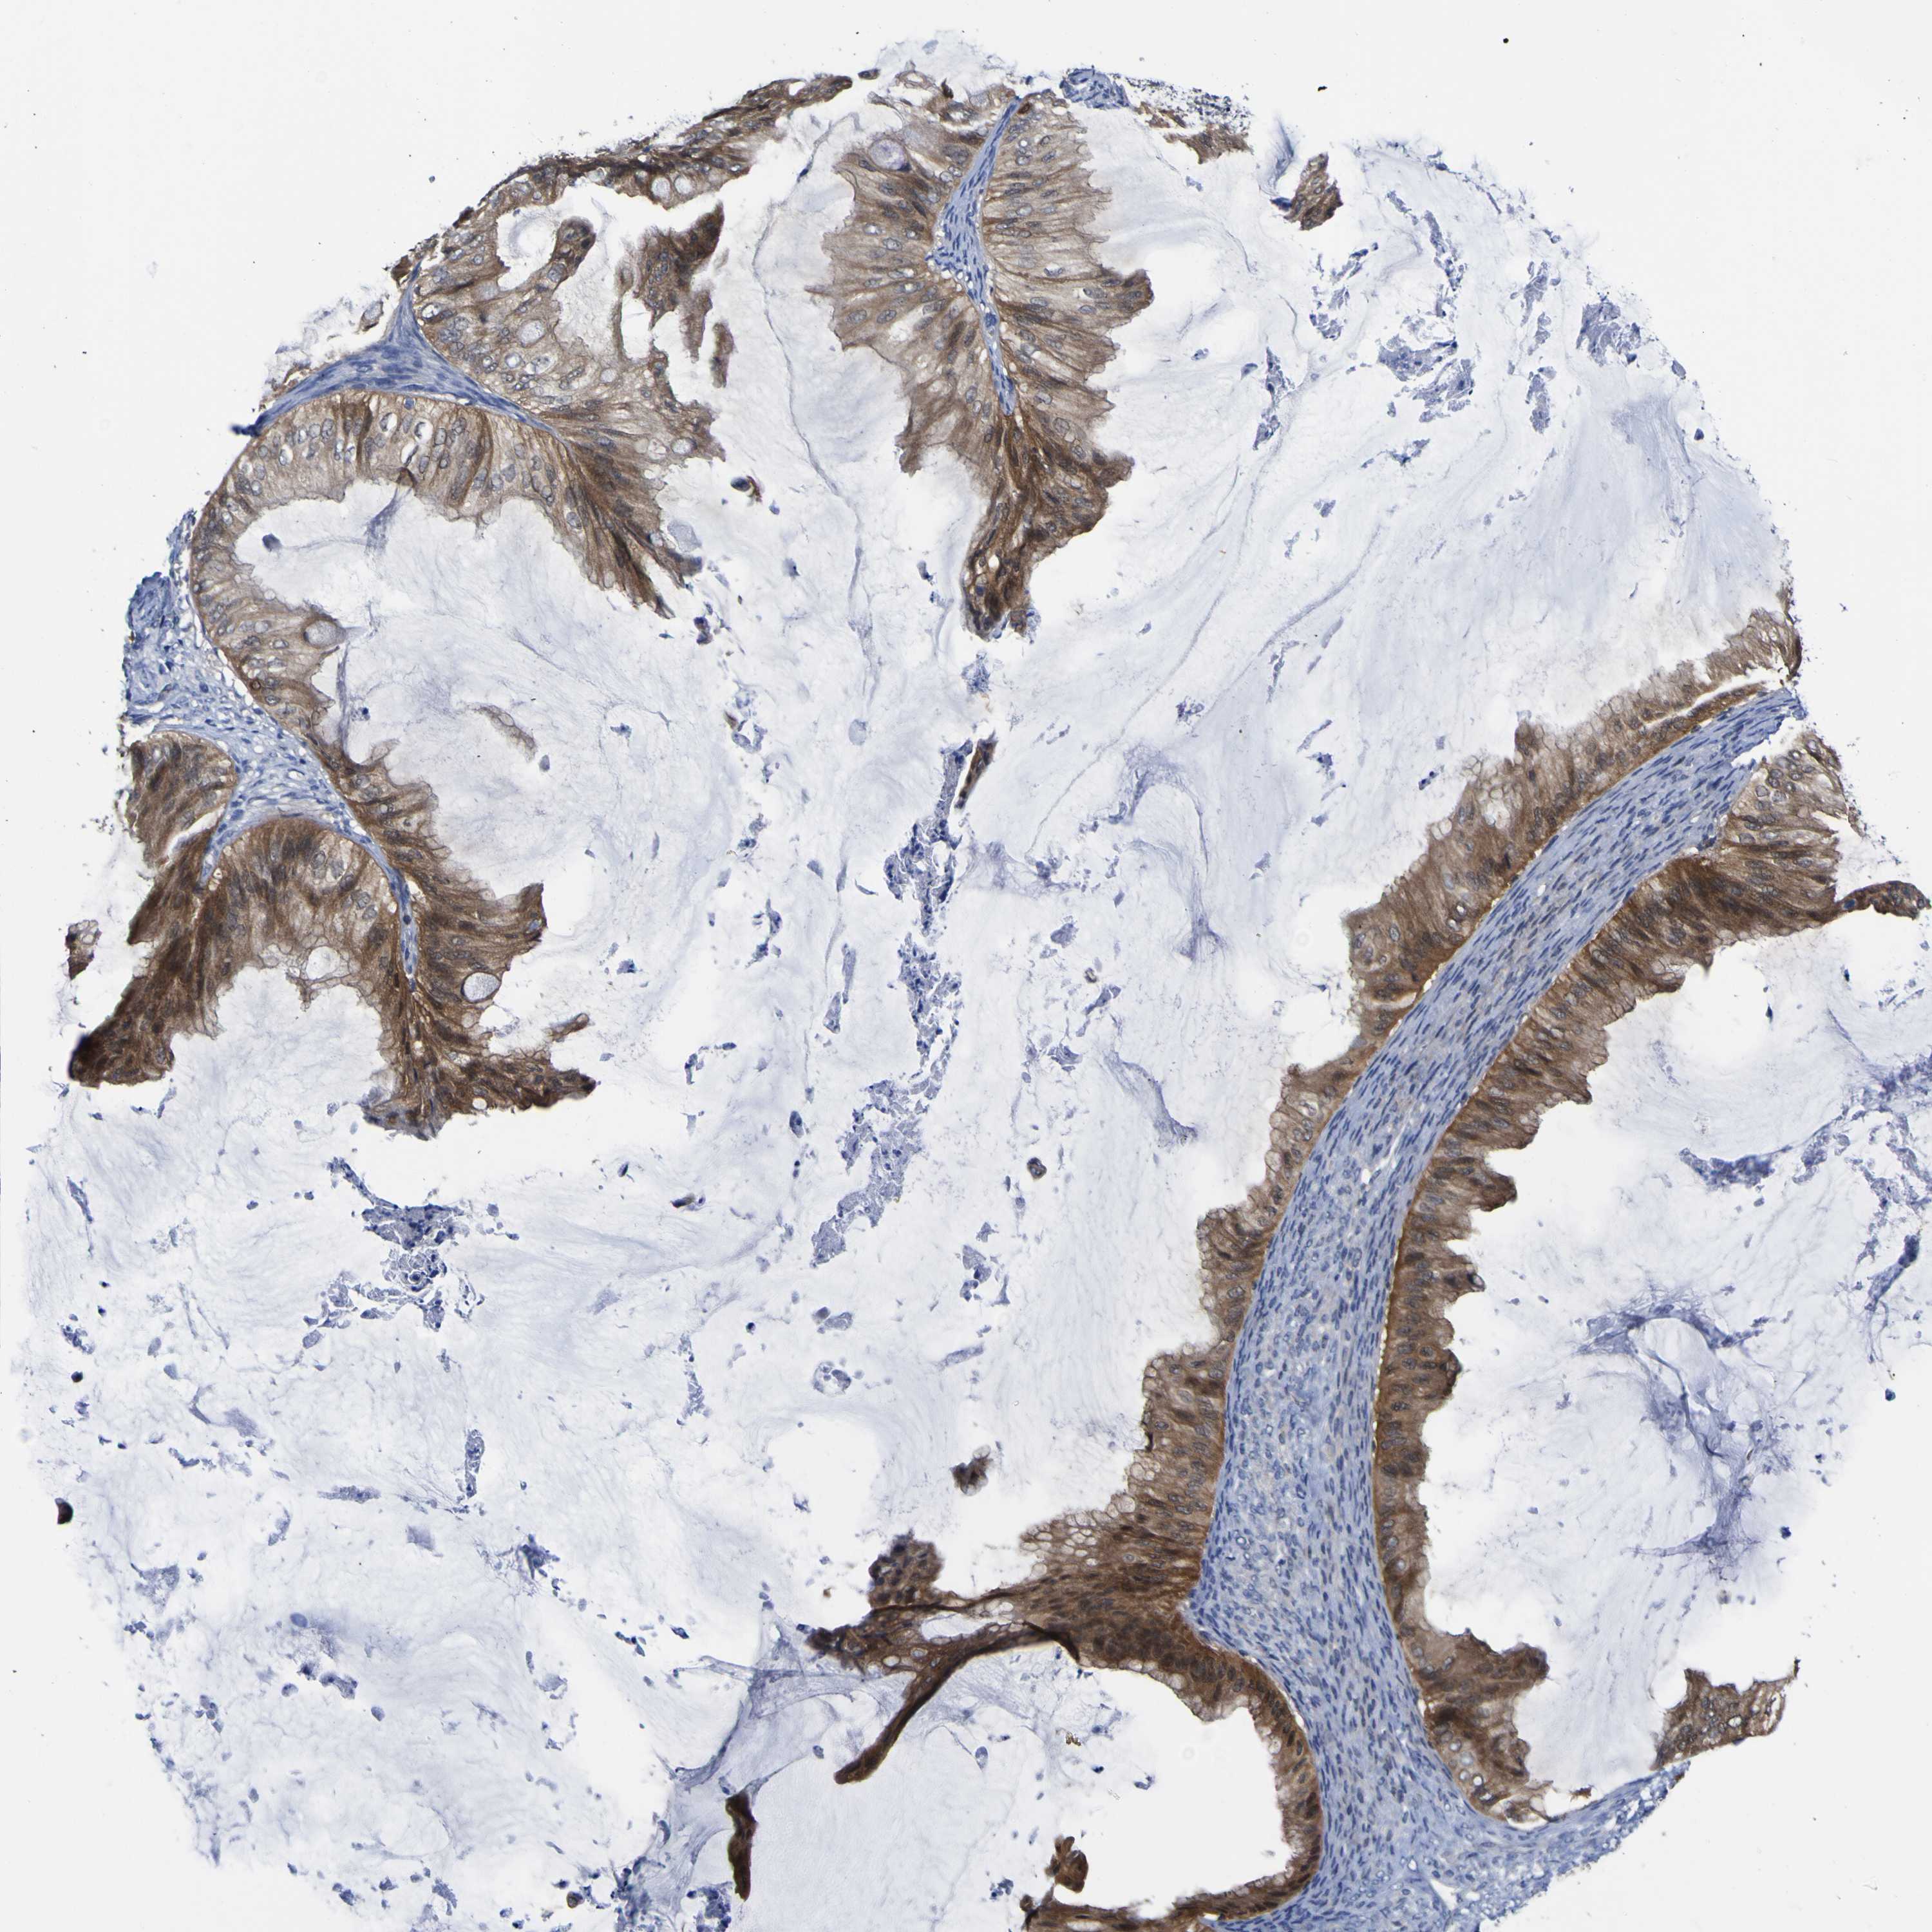

OVARIAN CANCER - Protein expressioni

A mouse-over function shows sample information and annotation data. Click on an image to view it in a full screen mode. Samples can be filtered based on level of antibody staining by selecting one or several of the following categories: high, medium, low and not detected. The assay and annotation is described here.

Note that samples used for immunohistochemistry by the Human Protein Atlas do not correspond to samples in the TCGA dataset.

Antibody stainingi

Antibody staining in the annotated cell types in the current human tissue is reported as not detected, low, medium, or high, based on conventional immunohistochemistry profiling in selected tissues. This score is based on the combination of the staining intensity and fraction of stained cells.

Each image is clickable and will lead to virtual microscopy that enables deeper exploration of all samples and also displays staining intensity scores, fraction scores and subcellular localization as well as patient and tissue information for each sample.

Antibody HPA011337

Antibody HPA024303

Antibody CAB003775

Cystadenocarcinoma, serous, NOS

Carcinoma, endometroid

Cystadenocarcinoma, mucinous, NOS

Carcinoma, NOS